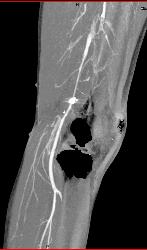

Liver Laceration and Bleed